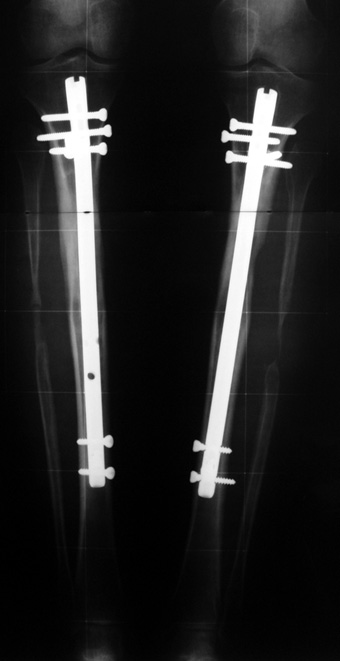

Biz son zamanlarda, seçilmiş vakalarda, uzatma sonrası uzunluğu ve “alignment’ı” korumak amacı ile unilateral dinamik aksiyel fiksatör ve kilitli intramedüller çivi kombinasyonunu tercih etmekteyiz. Bu yöntemin ön şartları medullanın en dar çapının 7 mm.’den geniş olması ve uzatma sonrası distalde en az 8 cm. uzunluğunda çivi kalabilmesidir. İntramedüller çivi hem uzatma esnasında femurun üzerine gelen makaslama ve bükülme kuvvetlerini nötralize etmekte hem eksternal fiksasyon süresini kısaltmakta, hem de yeni oluşan kemiği kırıklara karşı korumaktadır. Serimizde bir vakada subtrokanterik femoral osteotomi yapılmıştır. İntramedüller çiviye rağmen varus angulasyonu oluşması yönünde bir dezavantaj tespit etmedik.

İlizarov, distraksiyon osteogenezisi için endosteal kan dolaşımının önemini vurgulamıştır. Biz tüm vakalarımızda femuru oyarak intramedüller çiviyi çaktık; buna rağmen hiçbir vakada kallus oluşma süresi tahminimizden daha uzun olmadı. Bu yüzden medüller dolaşımın bozulmasına bağlı yeni kemik oluşma hızında bir yavaşlama olmadığını düşünüyoruz. Oyma sonrası meydana gelen revaskülarizasyon, intramedüller çivili fiksasyon stabilitesi ve erken fonksiyonel yüklenme bu gerçeğin temelini oluşturmaktadır. Eksternal ve internal fiksasyon yöntemlerinin kombine kullanımının potansiyel dezavantajları kan kaybının artması, intramedüller infeksiyon, yağ embolisi olasılığı ve aşırı metal yüküdür. Bunların içinde en çok korkulan problem bir çivi dibi infeksiyonun tetikleyeceği derin intramedüller infeksiyondur (panosteomyelit). Bizim serimizde bu yönde hiçbir komplikasyon gelişmemiştir. Bu olası komplikasyonun önlenmesi amacı ile uzatma sonundaki kilitleme medialden yapılmalıdır; ayrıca intramedüller çivi ve eksternal fiksasyon pinlerinin teması önlenmelidir.

İntramedüller çivi ve eksternal dinamik aksiyel fiksatör kombinasyonu teknik olarak standart İlizarov uygulamalarından daha zordur. Ancak şu avantajlar yöntemi cazip hale getirmektedir; eksternal fiksasyon süresinde kısalma, refraktüre karşı korunma, erken rehabilitasyon, azami hareket genişliği kazanma ve günlük yaşam konforu. Bu avantajlar artan maliyet , artan kan kaybı ve potansiyel derin infeksiyon gibi dezavantajların önüne geçmektedir. Sonuç olarak, bulgularımızın eşliğinde, intramedüller çivi üzerinden femoral uzatma tekniğinin güvenilir ve dayanıklı bir metod olduğunu ve bizce standart İlizarov uygulamalarına üstünlük sağlayan avantajlar getirdiğini söyleyebiliriz.